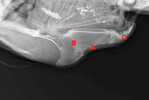

Brustbeinfrakturen und -deformationen sind zwei unterschiedliche Krankheitsbilder, die sich sowohl in ihrer Erscheinung als auch in ihrer Entstehung unterscheiden. Einige der zu beobachtenden Frakturen sind auf ein Trauma, d. h. durch starke Krafteinwirkungen, beispielsweise durch Kollisionen mit Haltungseinrichtungen oder Stürze, zurückzuführen. Diese traumatischen Frakturen sind durch Gewebeschäden und Einblutungen gekennzeichnet und können am gesamten Brustbein auftreten. Ein großer Anteil der Frakturen (je nach Studie bis zu 99 %) befindet sich jedoch im hinteren Drittel des Brustbeins. Anzeichen einer starken Krafteinwirkung sind hier häufig nicht sichtbar. Deshalb wird davon ausgegangen, dass es sich um nicht traumatische Frakturen...